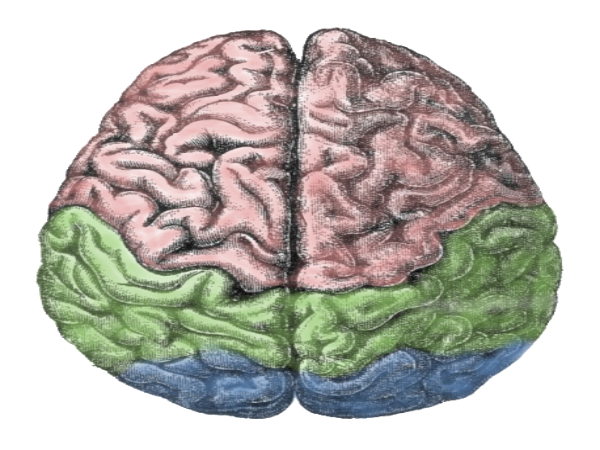

രണ്ട് തരം ടിഷ്യുക്കളാണ് മനുഷ്യന്റെ മസ്തിഷ്കത്തിലുള്ളത് - വൈറ്റ് മാറ്ററും(60%), ഗ്രേ മാറ്ററും(40%). ഇവ രണ്ടും വഴിയാണ് തലച്ചോറില് സിഗ്നലുകള് പ്രസാരണം ചെയ്യപ്പെടുന്നത്. ഗ്രേ മാറ്ററുകള് ന്യൂറോണുകള് അടങ്ങിയതും, സിഗ്നല് പ്രസാരണത്തില് പ്രധാന പങ്ക് വഹിക്കുന്നതുമാണ്. ഇവയ്ക്ക് സിഗ്നലുകള് അയക്കാനും സ്വീകരിക്കാനും കഴിയും.

മനുഷ്യന്റെ മസ്തിഷ്കത്തിലെ 90 ശതമാനം വരുന്ന നെക്രോട്ടെക്സ് ഒരു പ്രമുഖവും ശക്തവുമായ ഘടകമാണ്. സ്ഥിരമായ ബോധം നല്കുന്നത് ഇതാണ്. ടെംപറല്, ഓക്സിപിറ്റല്, ഫ്രണ്ടല്, പാരിയേറ്റല് ലോബ്സ് എന്നിങ്ങനെ നെക്രോട്ടെക്സിനെ വിഭജിച്ചിരിക്കുന്നു.